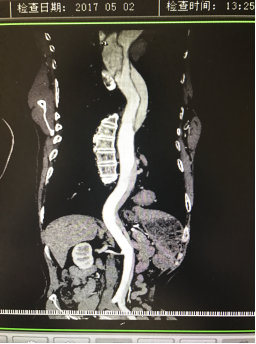

5月2號劉大伯照常早起干活,突然胸部劇烈疼痛,難以忍受,全身大汗,同時伴有右上肢發(fā)涼,他心想這次心絞痛比之前嚴重的多啊,趕緊叫上孩子到吉林國文醫(yī)院心血管內(nèi)科住院,患者長期高血壓病史,血壓一直控制不理想,大夫給他做了檢查,測左上肢血壓:82/45mmHg,右上肢血壓測不出,心率52次/分,右側(cè)肱動脈、尺動脈、橈動脈搏動消失,左側(cè)股動脈搏動較右側(cè)弱?!霸懔耍p側(cè)血壓差別這么大,是不是主動脈夾層了?”,接診大夫趕緊找來李主任,李主任反復(fù)詢問患者病情,表情突然凝重起來,患者胸痛這么明顯,血壓低的厲害,主動脈夾層的可能性很大。二話不說,李主任立即聯(lián)系影像科的醫(yī)生準備做主動脈CTA,移動患者做檢查的過程大夫們非常小心,嚴密監(jiān)測患者血壓變化情況。兩個小時后結(jié)果出來了,主動脈夾層從升主動脈一直撕裂到左側(cè)髂總動脈?。?!

從開始學醫(yī)到現(xiàn)在已經(jīng)快9年了,主動脈夾層患者也見過一些,但像劉大伯這種危險類型的還是第一次見到,心里真的為他捏把汗,撕裂的主動脈隨時都有可能破裂,生命隨時可能終止,要知道主動脈夾層的死亡率非常的高,約50%的患者發(fā)病后48小時死亡,約90%的患者發(fā)病1個月內(nèi)死亡。